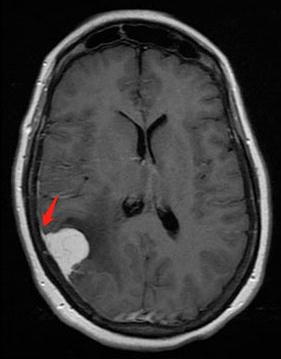

位于额叶的巨大脑膜瘤